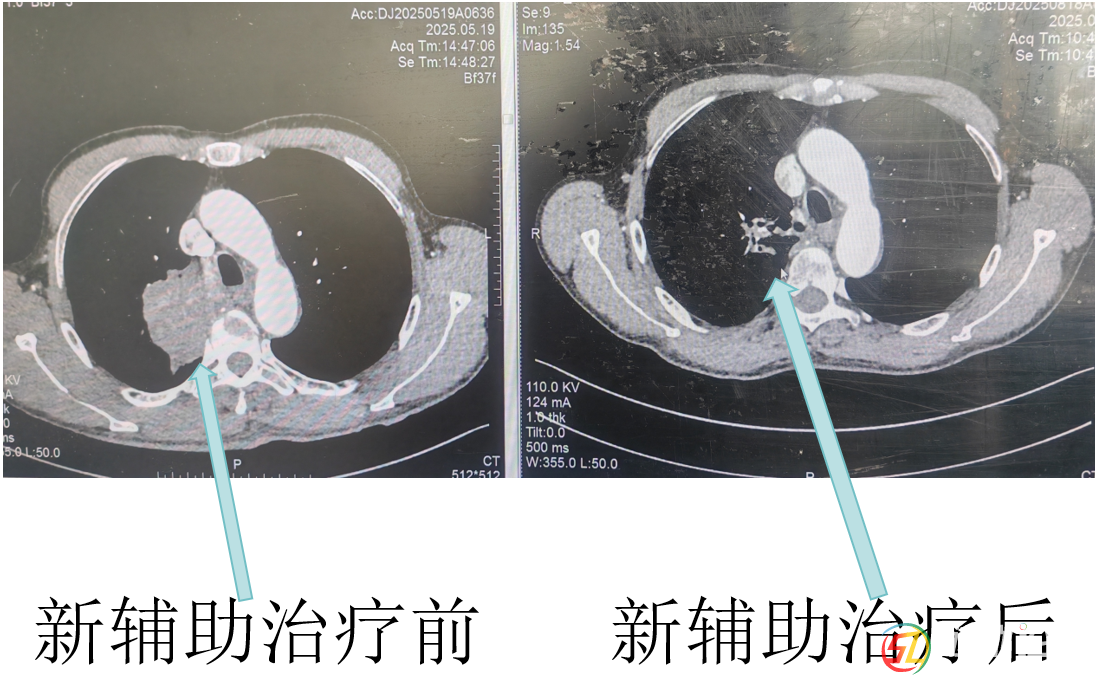

經(jīng)呼吸與危重癥醫(yī)學(xué)科醫(yī)生杜鵑三個(gè)周期的藥物治療后,復(fù)查CT顯示羅大爺肺上的腫瘤明顯縮小了!彭均偉判斷,現(xiàn)在手術(shù)有望完整切除腫瘤。就在大家看到希望時(shí),新的問題出現(xiàn)了。羅大爺有幾十年的老慢支和哮喘病史,肺功能檢查結(jié)果很差,根本達(dá)不到肺葉切除的手術(shù)標(biāo)準(zhǔn)。而且他三年前還因?yàn)樾呐K病做過冠脈支架手術(shù),長期服用阿司匹林,這又增加了手術(shù)出血風(fēng)險(xiǎn)。面對(duì)這些困難,彭均偉先為羅大爺制定了詳細(xì)的肺功能康復(fù)計(jì)劃,經(jīng)過一段時(shí)間的精心調(diào)理,羅大爺?shù)姆喂δ芙K于提升到了可以接受手術(shù)的水平。